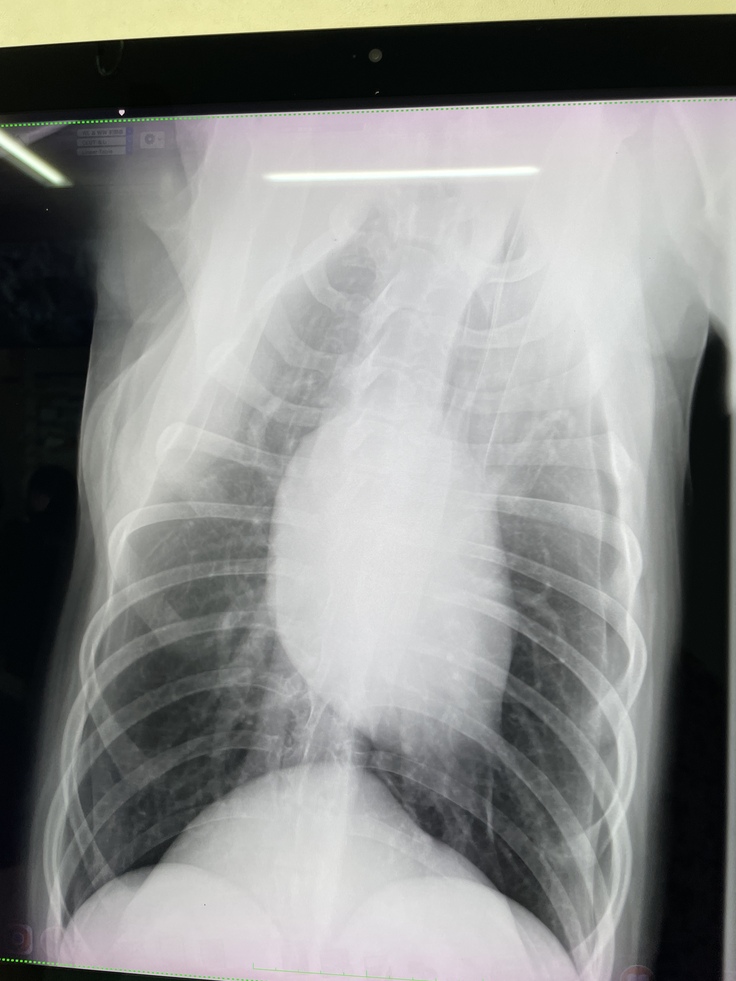

健診日でした!

今日は術後の定期検査の日でした!手と肺のレントゲンを撮ってもらいました☺︎3人がかりで鎮静剤無しでなんとかレントゲンを撮って頂けました✨費用もなるべく抑えて頂く努力をしてくださる病院の先生方に感謝です😢

モカも頑張ったね◎先生達にヨシヨシして貰ってご機嫌そうなモカでした♡肺の転移は初期とあまり変わらず、抗がん剤が上手く行ってるのかなと嬉しいお言葉を頂きました。このまま少しでも進行を緩やかにしていければいいなと思います。今回少し関節炎があるとの事で鎮痛剤の薬を貰いました。お薬増えちゃったけど頑張って飲もうね、モカ☺︎